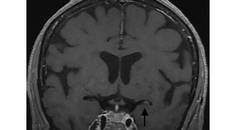

Stroke Snapshot: Intracranial MRI Vessel-Wall Imaging

Mitchell Barnes, DO; Parham Moftakhar, MDMitchell Barnes, DO; Parham Moftakhar, MD